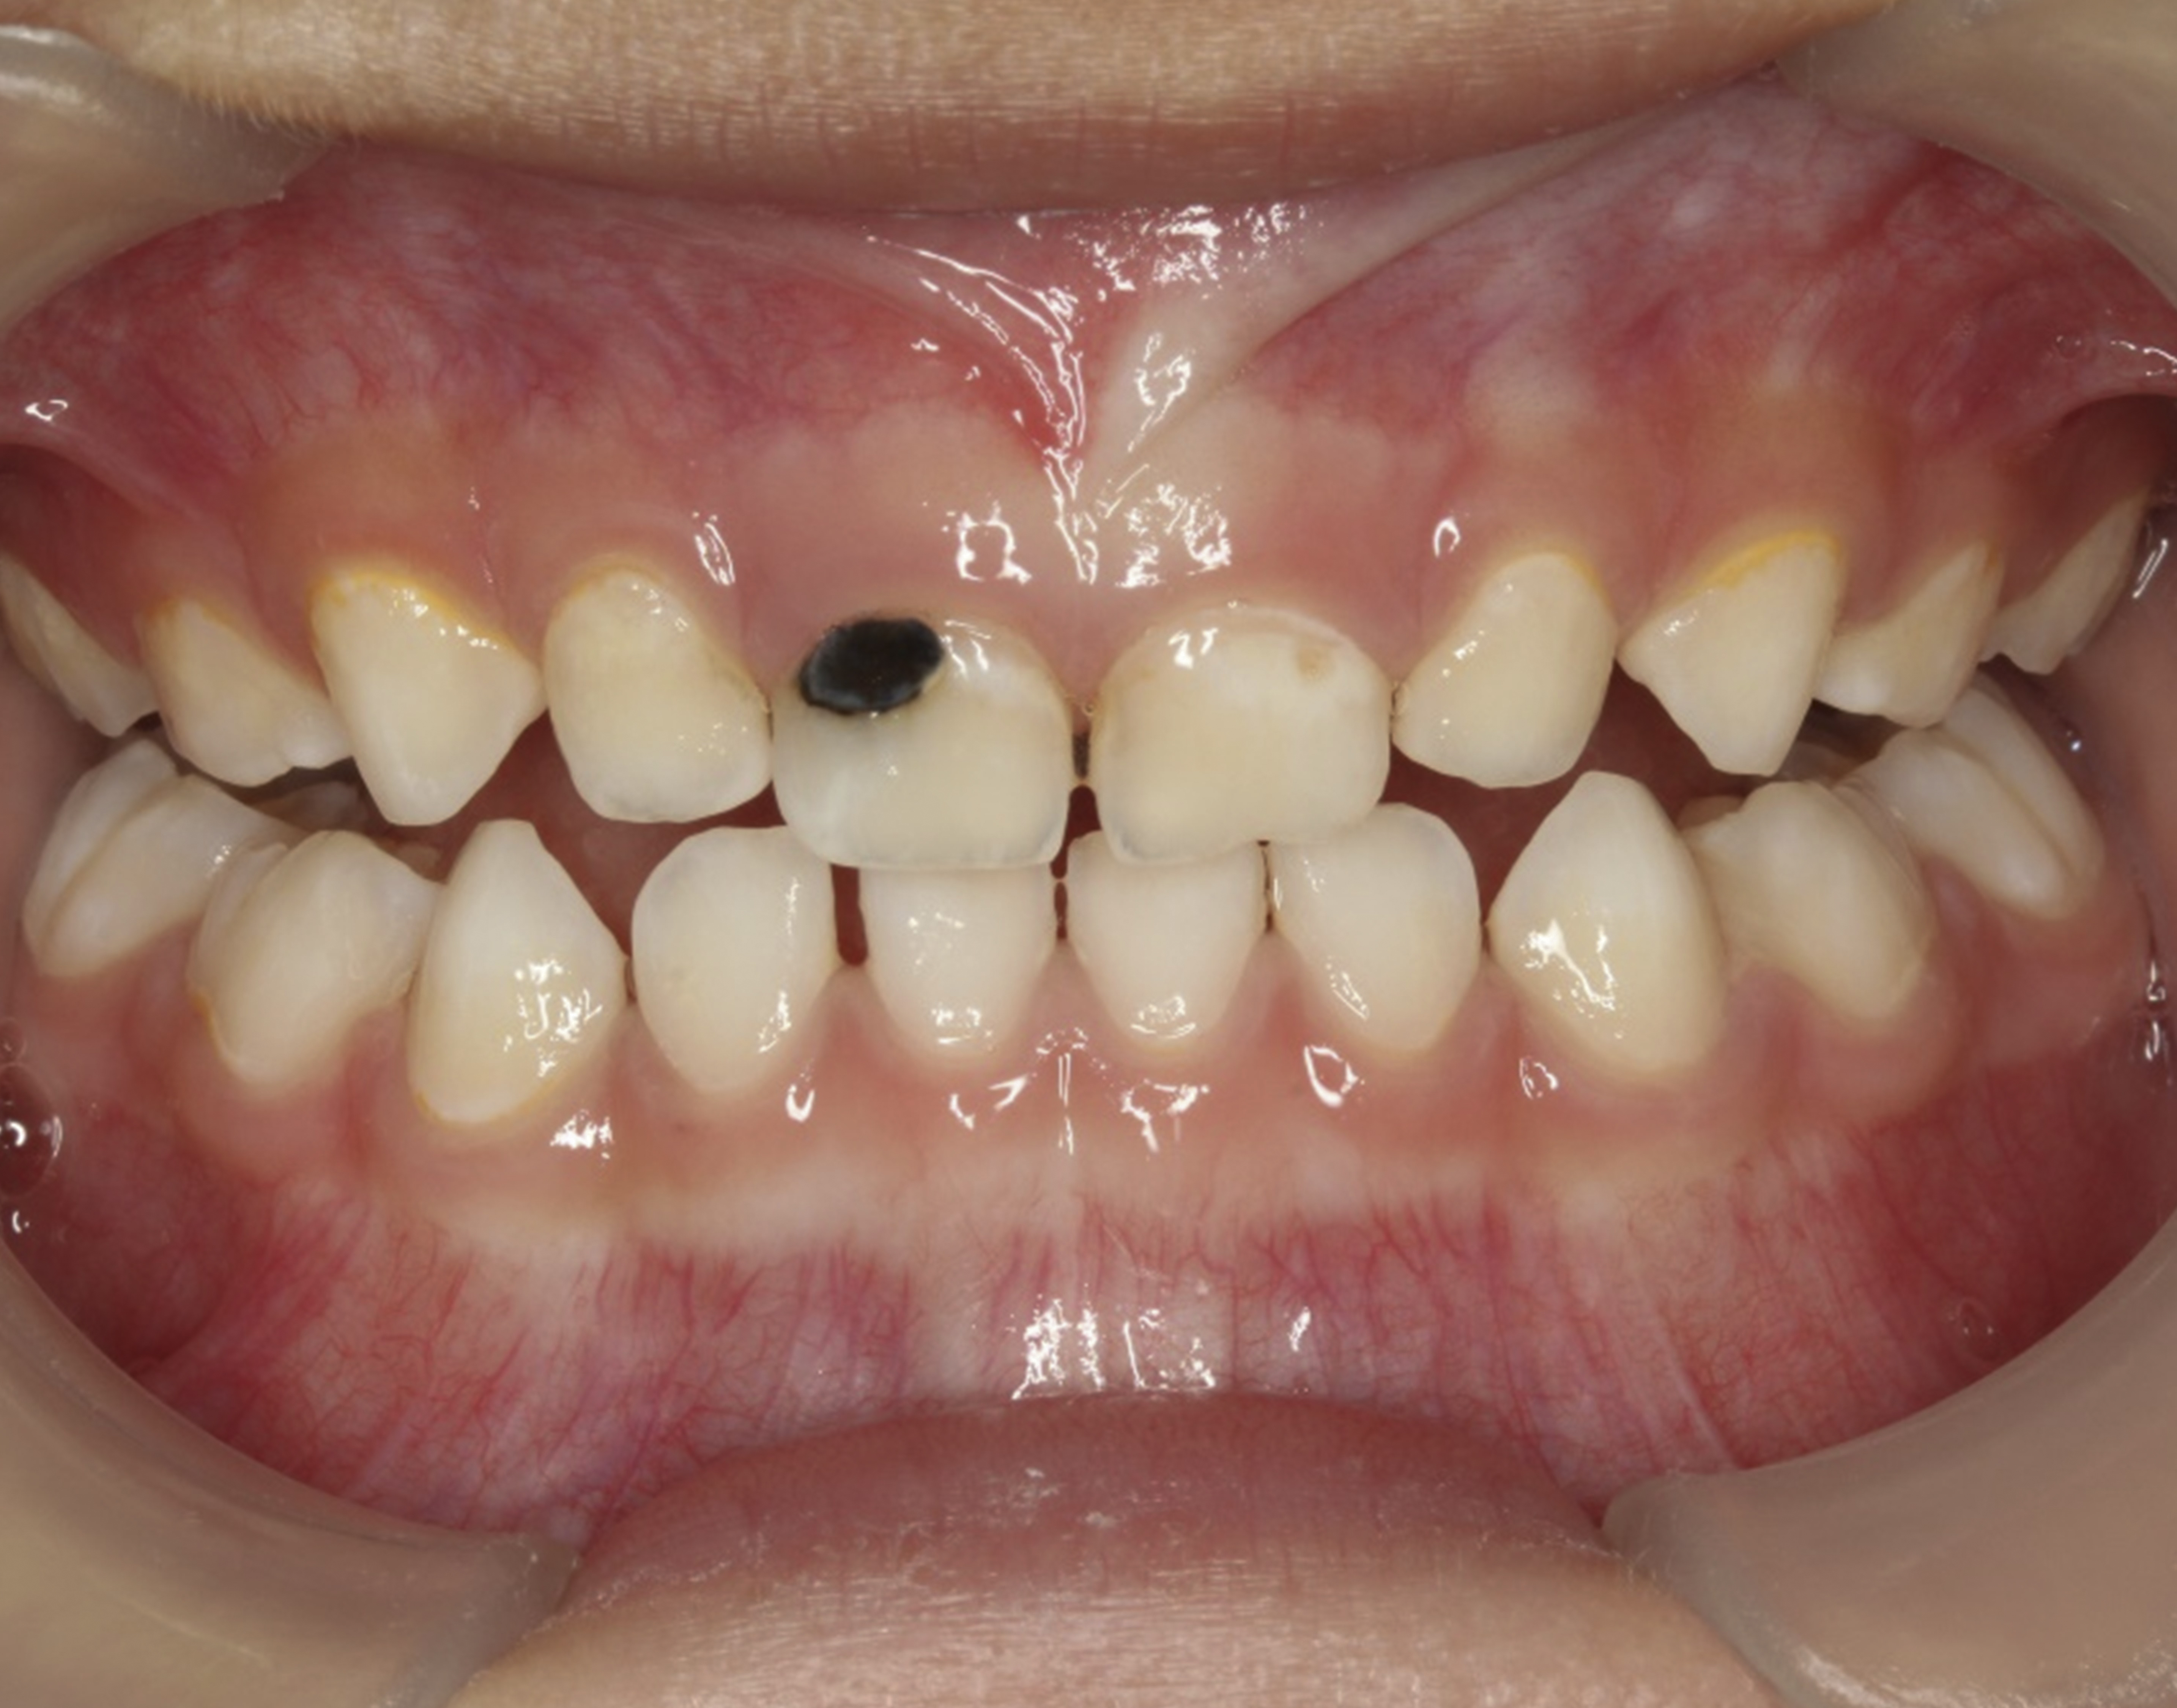

The inherent disadvantage of SDF is that the caries lesions will be stained black after SDF application. SDF stops caries progression by forming a hard, blackened, impermeable layer on the tooth surface that is resistant to caries (Figure 5 through Figure 9). The authors’ clinical observations are that the darker the color, the more likely the caries arrested. Some patients may not be pleased with the esthetics of this treatment outcome; therefore, it is important to inform the patients and parents (for child patients) about this treatment outcome. Moreover, SDF can stain clothes and the skin of the body. Though it does not cause any pain or damage, an SDF stain on skin cannot be easily washed away. It takes around 7 days for it to disappear, and the stain on clothes is permanent.22

Fig 8. Use of 38% SDF to arrest rampant caries in a young teenager. Fig 8: Pre-treatment intraoral frontal view of rampant caries. Fig 9: Frontal view of arrested caries after consecutive application of SDF for 3 weeks. (images from Chu, et al, 201436 [reprinted with approval])

Fig 9. Use of 38% SDF to arrest rampant caries in a young teenager. Fig 8: Pre-treatment intraoral frontal view of rampant caries. Fig 9: Frontal view of arrested caries after consecutive application of SDF for 3 weeks. (images from Chu, et al, 201436 [reprinted with approval])